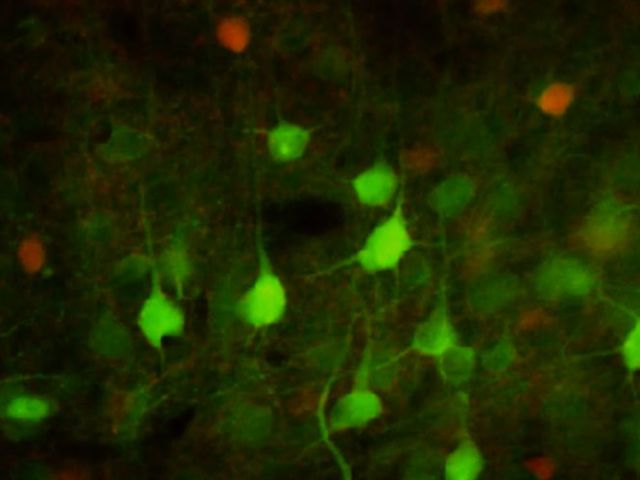

A ‘druggable’ mechanism of tau protein pathology could lead to new treatment for some of our most devastating neurodegenerative diseases.